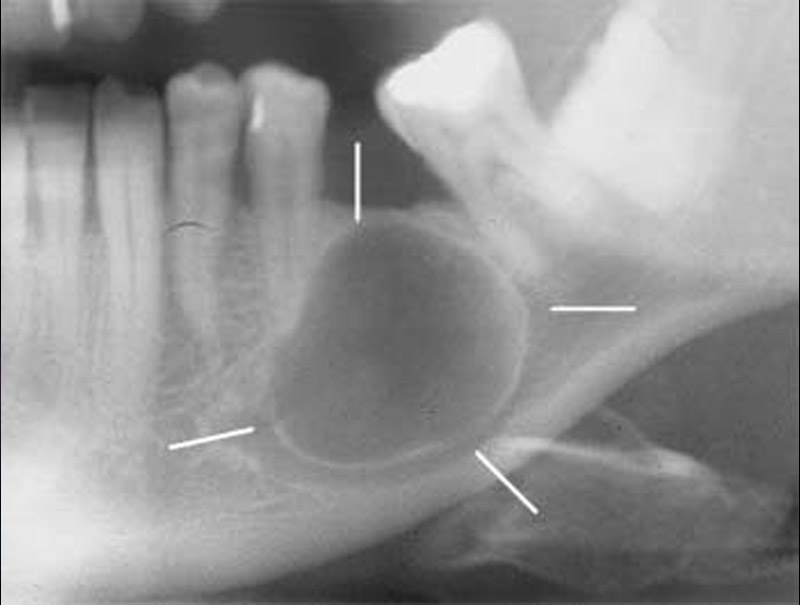

Odontogenik kistlər çənədə ən çox rast gəlinən törəmələrdən olub, başlanğıcını diş orqanından götürür. Bu törəmələr epitel hüceyrə qatı ilə döşənmiş zarla əhatə olunmuş, daxilində isə spesifik maye yerləşən kisəni xatırladırlar. Odontogenik kistlər ya xroniki iltihab nəticəsində ya da inkşaf anomaliyası nəticəsində yarana bilir.

İnkşafı və böyüməsi tədricən baş verdiyindən, bu proses pasiyent tərəfindən demək olar ki hiss edilmir. Yalnız törəmənin ciddi ölçülərə çatması nəticəsində və ya iltihablanması nəticəsində meydana çıxan kliniki əlamətlər nəticəsində aşkarlanır. Əksər hallarda isə çəkilən diş və çənə rentgen şəkillərində təsadüfən rast gəlinir.

Törəmələrin müalicəsi onun növünə, yerləşməsinə, ölçüsünə, pasiyentin yaş və sağlamlıq durumuna görə seçilir və icra olunur. Müalicə prinsipi bütün hallarda nəticə etibarilə, törəmənin kənarlaşdırılmasına əsaslanır. Müalicə çox zaman yerli ağrısızlaşdırma altında bəzən isə (məsələn, böyük ölçülü kistlərin müalicəsində) ümumi ağrısızlaşdırma altında aparılır. Müalicənin gecikdirilməsi və ya təxirə salınması kistlərin daha da böyüməsinə, nəticədə ciddi miqdarda sümük itkisinə səbəb olur. Müalicənin natamam aparılması leziyonun yenidən təkrarlanmasına (residiv) səbəb ola bilir.